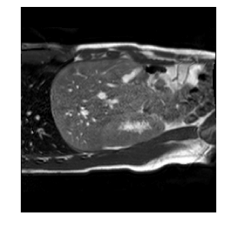

Qualitative results are shown in Fig. 4. We observe no large qualitative differences in the performances of MFIN and MFINc for either loss function. Since, MFINc-SSIM provides the best quantitative results, we show interpolated images from this method and compare them against SCIN-SSIM. Both methods perform well when the motion between the neighbouring images is low. This is reflected in the absence of any structures in the error images in Fig. 4.1. However, RMSE is lower for SCIN because it produces a denoised interpolated image, while MFIN carries over the noise pattern from the neighbouring known image. Whenever there exists high motion between the images being interpolated, SCIN produces blurry images and often misses image structures. This can be observed in cases 2-4 in Fig. 4. For all these cases, MFINc (and also MFIN) produces sharp images and largely preserves structures in the images. Fig. 4.2 shows a case where MFINc additionally has a much better performance with respect to image alignment. Fig. 4.3 shows a representative case, with small improvement in image alignment, yet worse RMSE and SSIM values for MFINc. Finally, Fig. 4.4 shows a case, where MFINc produces worse alignment of structures than SCIN.

14.13, 0.81 13.02, 0.84

2)

9.16, 0.76 10.12, 0.74

3)

9.75, 0.85 12.94, 0.81

4)

a b c d e